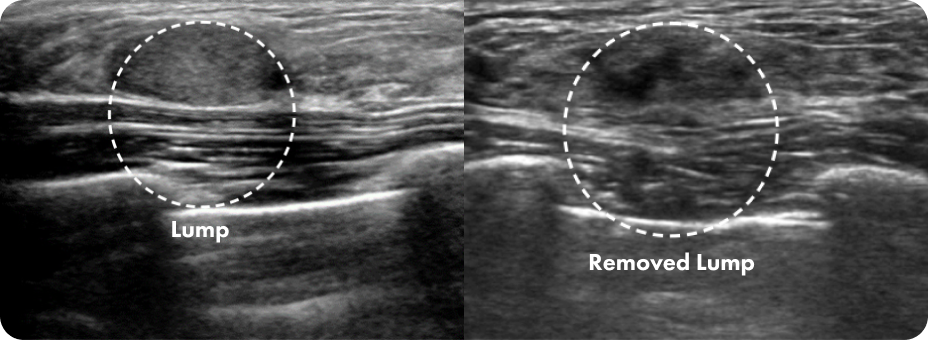

Before and After Lump Removal

Using ID’s advanced Mammotome technology, we accurately determine the density of the

patient’s breast tissue and any implants before planning a customized 1:1 procedure.

Even after breast augmentation surgery, there is no need to worry about damaging the implants.

Our breast disease specialists perform the Mammotome procedure using

minimally invasive incisions for safe and precise treatment.